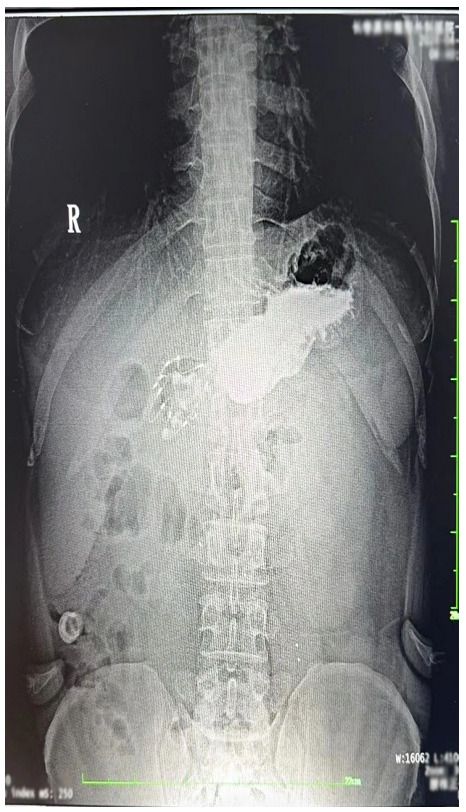

术后的观察期,我感觉胃部有些异物感,但在可忍受的范围。于是静滴结束后,我就回家了。路途中轻微颠簸加重了胃部的不适感,通过平卧休息后不适感逐渐缓解。次日清晨,我感觉麻醉的影响基本消失,身体恢复如常。为了确认支架置入的情况,我在医院复查了上消化道造影,造影显示支架系统顺利展开,位置正确。这一刻,我心中悬着的石头落地,随即我便投入到工作中(特别说明:此行为基于个人职业的特殊性,我建议普通患者术后还是要充分休息)。

上消化道造影照片